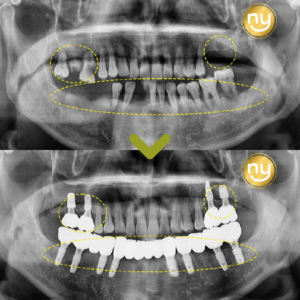

울산안아픈치과 신경치료 후 염증 치아재식술로 해결해요! 안녕하세요. 울산안아픈치과 뉴욕연합치과입니다. 임플란트가 워낙 보편화되고 선호하는 분들이 많아지고 있지만, 자연치아를 살리고자 하는 수요도 급상승하고 있는 추세입니다. 위 환자분은 충치가 많이 진행되어 신경치료한 치아를 사용하고 있었습니다. 하지만, 오랜 기간이 지나 치아 뿌리 끝에 염증이 생겨 발치를 권유받았는데요, 발치를 하더라도 치아 뿌리만 손상 더보기…